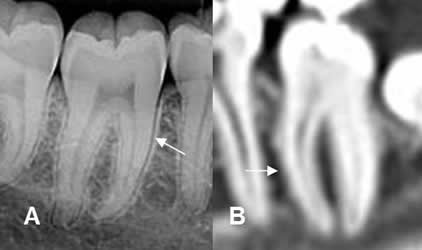

La dentina de los dientes, tiene una densidad similar a la cortical del hueso. El cemento a nivel de la corona, se identifica como una delgada capa, mas densa que la dentina. (1, 4, 6, 8). La raíz, el conducto radicular y la cámara pulpar, son menos densas y ocupan la zona central. (1, 3, 4, 8). (Fig 13).

Fig 13. Diente normal.

A y B: TAC reconstrucción sagital. Dentina, con similar densidad que la cortical del hueso. (Flechas delgadas). Cemento mas denso, en la corona del diente. (Flecha gruesa). Cámara pulpar y conducto radicular, menos densos. (Punta de flecha).

Fig 14. Ligamento periodontal normal.

A: Rx periapical y B: TAC reconstrucción sagital. Imagen radiolúcida entre la dentina y la lámina dura, que corresponde al ligamento periodontal. En B, se identifica el espacio periodontal radiolúcido.